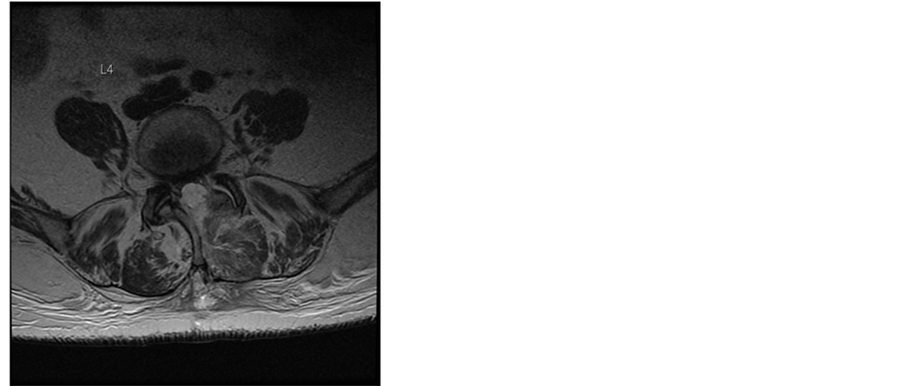

Additionally the patient had various comorbidities in her medical records. The acetylsalicylic acid medication, prescribed from her cardiologist because of a coronary heart disease, was discontinued following our routine protocol 7 days before the surgery was scheduled. The operation itself was uneventful. The patient received general anesthesia with systemic opioid analgesics. An interlaminar access was performed at level L2/3, L3/4 and L4/5, the rezessal nerves were released by removing parts of the ligamentum flavum and the internal surface of the hemi-laminae. Perfect local haemostasis was performed as usual, and no Redon drain was inserted therefore. Due to early mobilization and apart from age no additional risk factors, she got no thrombosis prophylaxis according the 2009 guidelines of the Association of the Scientific Societies in Germany [6] . In the first day the postoperative course was uneventful. The analgesic regime was prescribed according to our local routine, containing opioids, 4 g paracetamol and up to 4 g metamizol in 4 single doses per day and the patient was not anticoagulated to prevent thromboembolic issues. Our patient recovered quickly and the analgesics could be reduced, leaving only metamizol and low dose opioids. The patient was already fully mobilized. On day 3 the local pain increased again and at the same time it became increasingly radicular. Due to calf pain she received 40 mg enoxaparine as a single dose that was stopped thereafter as soon as a deep venous thrombosis was ruled out via compression ultrasound. On the same day we performed an MRI of the spine and discovered a big epidural hemorrhage on L2/3 to L4/5 with compression of the dural sac (Figure 1).

Figure 1. T2-weighted MR images of the lumbar spine 4 days after surgery. Sagittal and axial MR images at L4/5 level demonstrate an acute multisegmental epidural bleeding between L2/3 to L4/5 levels with almost complete obliteration of the spinal canal and severe compression of the dural sac.